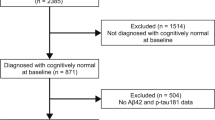

Forty eight EOAD (MMSE ≥ 15; A + T + N +) and forty two age-matched healthy controls (HC; A − T − N −) from a prospective cohort underwent full neuropsychological assessment, 3T-MRI scan and lumbar puncture at baseline. Participants repeated the cognitive assessment annually. We used linear mixed models to investigate whether baseline cortical thickness (CTh) or subcortical volume predicts two-year cognitive outcomes in the EOAD group.